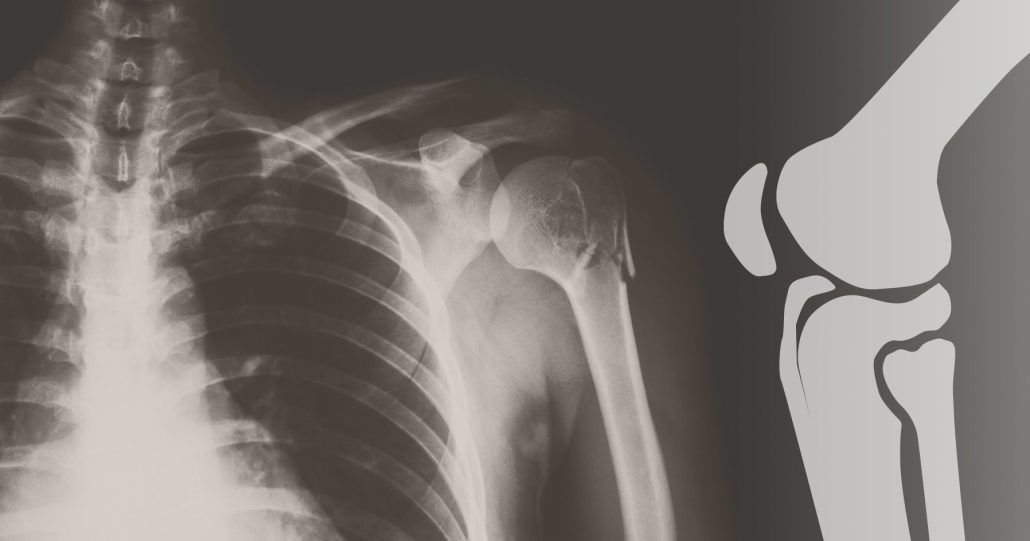

عملکرد DEXA بر اساس استفاده از دو منبع پرتو ایکس با انرژیهای مختلف است. در این روش، پرتوهای ایکس به استخوانها تابیده میشوند و با توجه به میزان جذب این پرتوها توسط استخوان، دستگاه میتواند تراکم استخوان را تعیین کند. هر چه تراکم استخوان بیشتر باشد، میزان انرژی که جذب میشود، کمتر خواهد بود. با تحلیل دیتاهای بهدستآمده، پزشکان میتوانند به نتایجی درباره وضعیت استخوانها و سلامت کلی بیمار برسند.

مکانیسم عملکرد DEXA (Dual-Energy X-ray Absorptiometry) به صورت علمی و مهندسی طراحی شده است که برای تحلیل و اندازهگیری تراکم استخوان مورد استفاده قرار میگیرد. این روش از تابش دو نوع اشعه ایکس با انرژیهای مختلف بهره میبرد. وقتی که این اشعهها به استخوانها تابانده میشود، با توجه به ترکیب مواد در استخوان، بخشهای مختلفی از اشعه جذب و یا عبور میکند. استخوانهای سالم با ساختار متراکمتر، اشعه بیشتری را جذب میکنند در حالی که استخوانهای با تراکم کمتر و احتمالاً آسیبدیده، این اشعهها را کمتر جذب میکنند.

دستگاه DEXA دو تابش با انرژیهای مختلف را به کار میبرد که به طور معمول به نامهای “هیدروکسیل” و “پیکونیت” شناخته میشوند. با توجه به تفاوتهای ناشی از جذب اشعههای مختلف، دستگاه قادر است تا به طور دقیقتر تراکم معدنی استخوان را اندازهگیری کند. این فرآیند به واسطه تجزیهوتحلیل دو نوار انرژی صورت میگیرد، که در نهایت حجم و غلظت مواد معدنی استخوان مانند کلسیم را تخمین میزند.